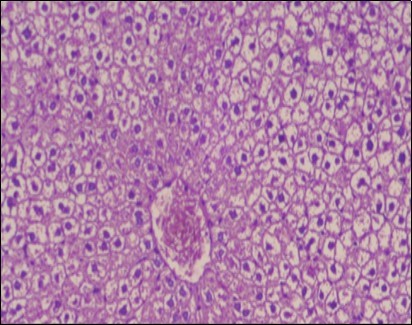

Effect of Ator, Fennel and Their Combination on the Histology of the kidney of the Obese Rats

The histological examination of the kidney of the control rats fed on a standard diet showing normal rounded capsules with normal Bowman's glomeruli, round proximal tubules and elongated distal tubules with high cuboidal cells figure 1. The rats fed (HFD) showed fatty degeneration of the tubules with eosinophilic material deposition, glomerular atrophy with wide urinary space and distal tubules with extrusion of nuclei into lumen figure 2. By comparison kidneys of rats which were treated by fennel after being obese and the control rats observed partial improvement in both Bowman's capsules and proximal tubules. Note the distal tubules show less focal fatty infiltration figure 3.While examination of rats kidney that were treated by ator after obesity showed improvement in Bowman's capsules with normal glomerular and partial improvement in proximal tubules and distal tubules, figure 4. Kidney of rats that were treated by fennel and ator after obesity and the control rats showed high improvement in the tissues with normal glomerular and that Most of Bowman's capsules and renal tubules, restoring their normal appearance figure 5.

Figure 2.Photomicrogragh of kidney section of obese rat showing fatty degeneration of the tubules with eosinophilic matrial deposition, glomrerular atrophy with wide urinary space and distal tubules with extrusion of nuclei into lumen , (H&E) (40X).

Photomicrogragh of kidney section of obese rat showing fatty degeneration of the tubules with              eosinophilic matrial deposition, glomrerular atrophy with wide urinary space and distal tubules with                 extrusion of nuclei into lumen , (H&E) (40X).